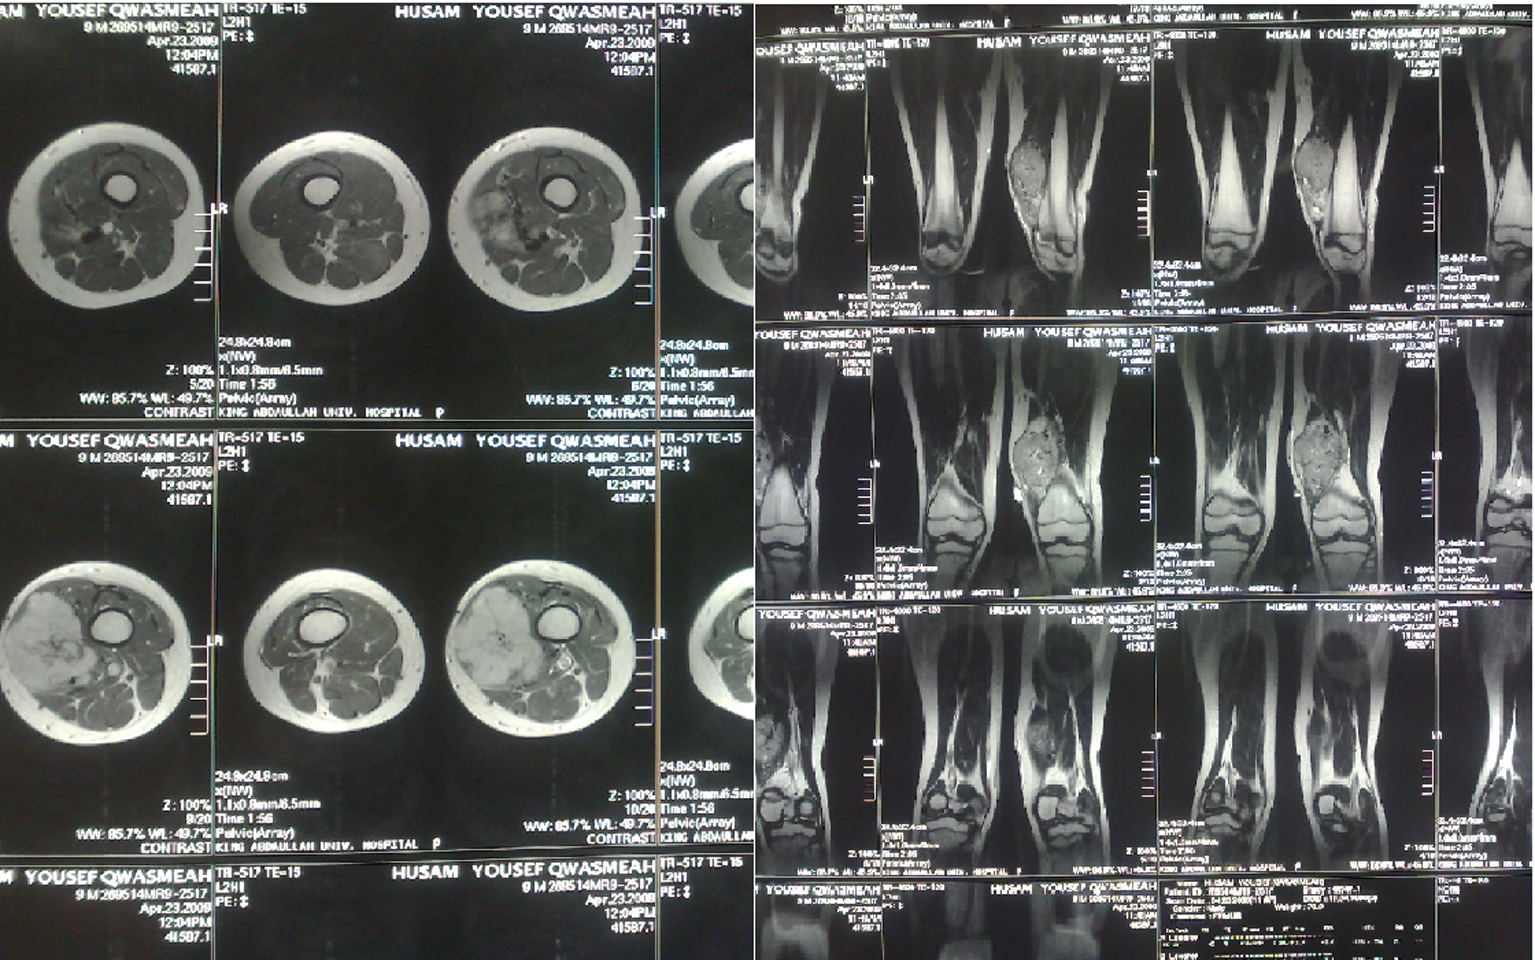

Magnetic resonance imaging (MRI) of the left thigh, performed later in the same week, revealed a well-defined soft tissue mass, heterogeneously enhanced, measured 6.5 × 4 × 10 cm, displaced and invaded the lower vastus medialis muscle. There was no involvement or invasion of underlying bones and no evidence of a periosteal reaction (Fig. 2). The superficial femoral vein and artery were displaced laterally.

![]() Click for large image | Figure 2. Pre-operative MRI findings. |